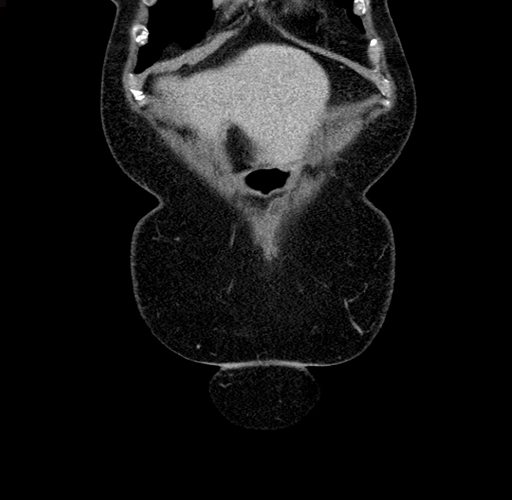

MRI T1